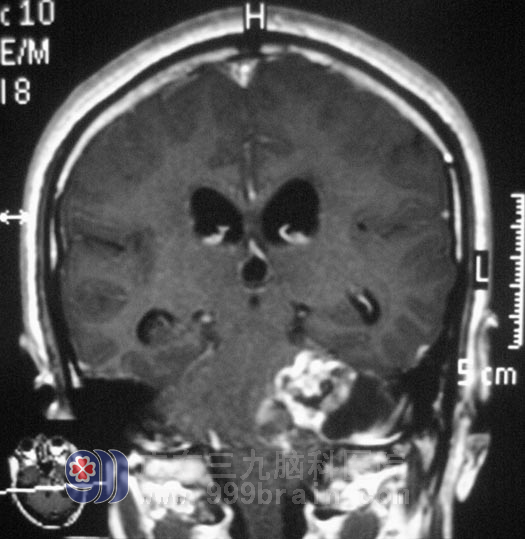

谢先生在一年前开始出现左耳听力变差,未行检查治疗,左侧听力进行性下降,伴间断性伴头痛,可忍受。头颅MRI结果提示:左侧桥小脑角区囊实性占位,考虑神经鞘瘤可能。

10月27日,广东三九脑科医院综合神经外科 鲁明主任主刀,在全麻下行左侧桥小脑角占位切除术+颅内压探头植入术,在显微镜下探查见桥小脑角鱼肉状肿瘤,包膜完整、血运丰富、质软、边界尚清,见肿瘤向前深入内听道,术中对三叉神经、后组颅神经等保护完好,手术顺利结束。术后病理结果为:(左侧桥小脑角区)神经鞘膜瘤。